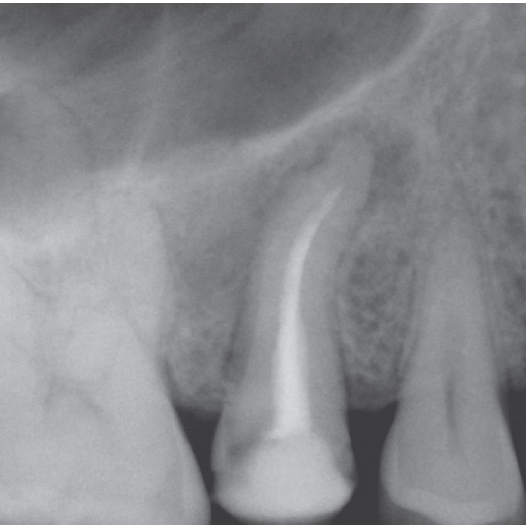

Before

Before Root Canal treatment